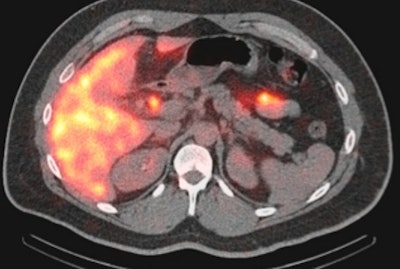

SPECT/CT image of a 35-year-old woman with a small bile leak at the cholecystectomy site. Image courtesy of Dr. Elham Safaie.The average additional scan time for SPECT/CT ranged from 20 to 30 minutes, depending on the patient's dose and his or her situation, Safaie said. That added scan time is "reasonable even in an emergency setting," she added.